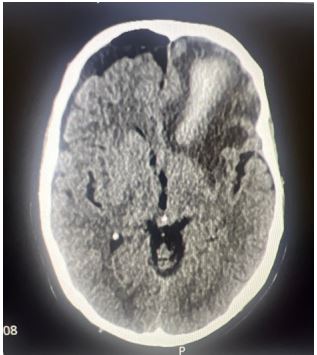

Neurosurgical review advised conservative management with IV antibiotics and close monitoring. Serial imaging showed a progressive reduction in pneumocephalus.

Figure 2: Follow-up CT showing reduced pneumocephalus and improving mass effect.